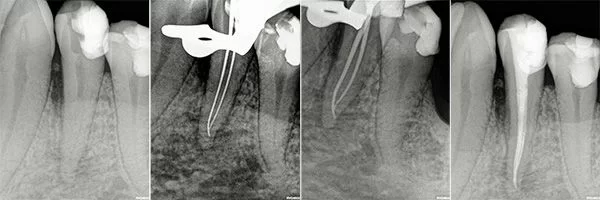

Root Canal in Morocco Before and Afters

Certified Endodontists with Microscope and Laser.

Check out our Before and Afters

Root Canals are done by an Endodontist and require the Specialist to make a hole through the enamel and dentin surfaces to gain access to the pulp chamber, where the Endodontist proceeds to remove the pulp, clean the pulp chamber and seal the chamber with gutta-percha. To ensure the long-term success of the tooth after a Root Canal an antibiotic is prescribed and a Post and Core Build-Up and Crown are recommended to prevent fractures or filtration of bacteria to the tooth.

Step-by-Step Root Canal Procedure

- At the beginning of the procedure, the dentist will isolate the tooth using a rubber dam and anesthetize the tooth sufficiently to prevent pain while performing the procedure.

- The dentist uses a drill to access the pulp chamber and related canals of the tooth. This allows inserting specialized dental instruments to clean the pulp chamber and root canals. Then the specialist cleans completely the remaining space and shapes it to make space for a filling. The filling will replace the pulp in the tooth.

- The dentist fills the Root Canal with a bio-compatible material. Gutta-percha and Adhesive dental cement are good options to seal the root canal. Sealing prevents future infections in the area.

- A temporary filling is placed in the hole used to access the root canals. Once the dentist deems the tooth is healing properly and the root canal is a success, he places a permanent restoration.